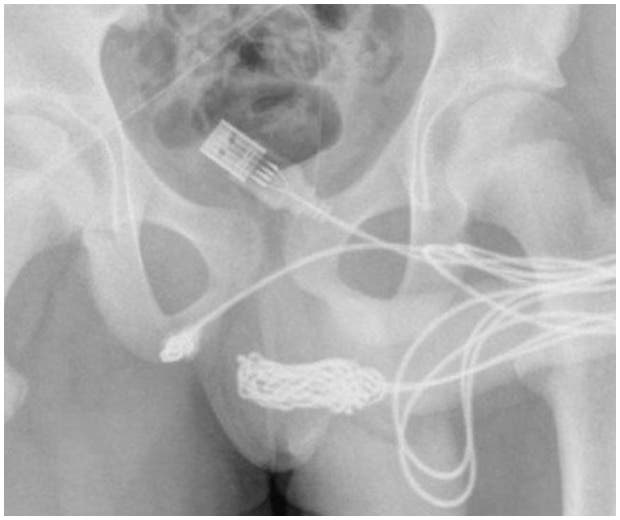

Um jovem de 15 anos precisou realizar uma cirurgia de emergência após inserir um cabo USB no pênis para medir o órgão. O morador de Londres foi levado ao hospital após urinar uma grande quantidade de sangue.

Os médicos cortaram os músculos ao redor do pênis e do escroto e retiraram o objeto. (Ibahia)

*Foto: Reprodução